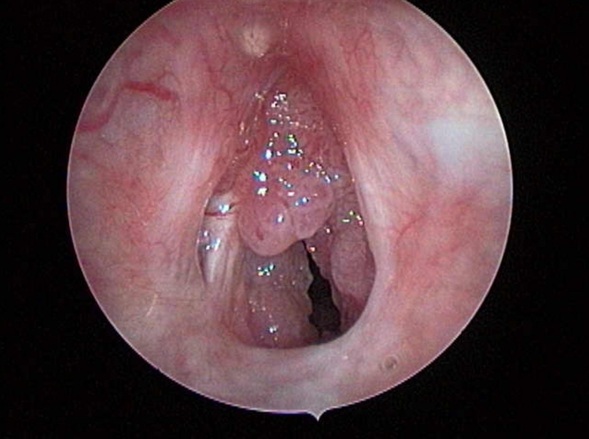

Hình 1. Hình ảnh Papilloma

Nội soi họng: Khối papilloma màu hồng, dạng sùi nhiều thùy, bề mặt không chảy máu, chiếm gần trọn thanh môn.